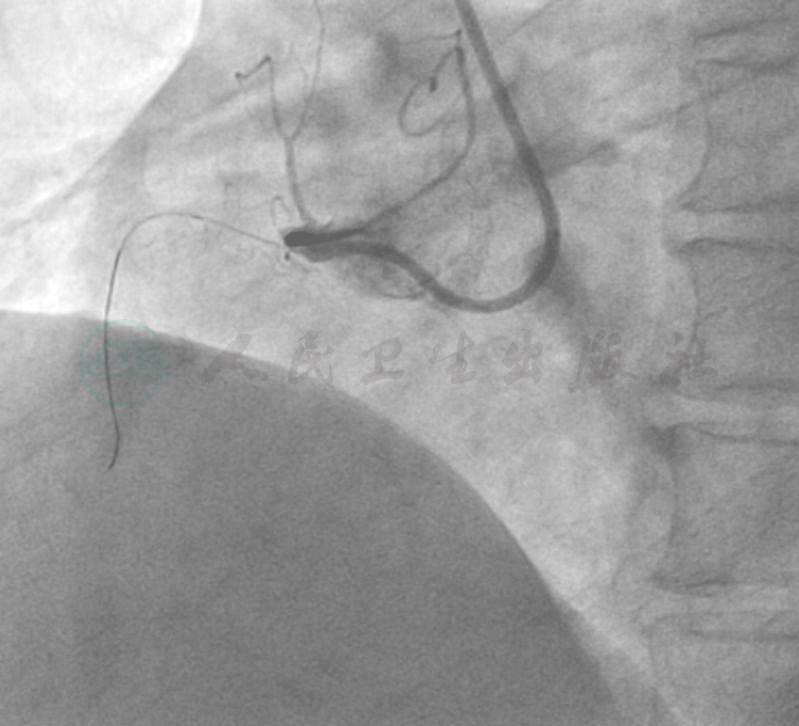

经右侧桡动脉径路,5F TIG造影管。造影结果:左冠状动脉慢血流,TIMI血流2级,未见明显侧支循环至右冠状动脉;右冠状动脉在近段完全闭塞,通过自身桥侧支可见中远段隐约显影(图1~图4)。

图3 右冠在近段完全闭塞,通过自身桥侧支可见中远段隐约显影

图4 右冠在近段完全闭塞,通过自身桥侧支可见中远段隐约显影